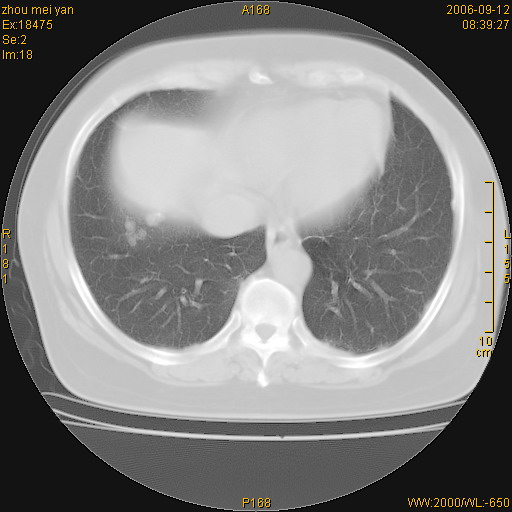

患者、女、55岁。因心率失常住院检查ct发现胸部多发结节。腹部b超肝、胆、胰、脾、肾、子宫附件未见异常。无结核病史,无粉尘接触史。请大家来会诊。谢谢!

病变位于胸膜,多发结节,边界清楚,内见小结节状钙化。其它未见异常。

双侧胸膜多发结节,形态不规则,边缘较清楚,每一个结节中心似乎都有钙化点的特征,与胸膜广基相切。临床无结核病史,无粉尘接触史。

影像表现十分有特点:双侧肋胸膜及膈胸膜广泛散在分布大小在2至6mm左右,较大病灶中心可见钙化。

考虑恶性胸膜间皮瘤可能性大,病灶位于胸膜,以宽基地与胸膜相连,呈结节样改变,部分病灶内可见点状钙化影。请各位老师多多指导!

我认为该病例不考虑是1:胸膜间皮瘤{1,胸膜的增生分布范围较广。2,其内有钙化,在胸膜间皮瘤中钙化的发生很少}。2:结核性胸膜炎后遗症也不考虑{结核性胸膜炎一般都会引起胸腔的积叶和临近肺实质的改变}。

双侧肋胸膜及膈胸膜广泛散在分布大小不等结节影,较大病灶中心可见钙化。

如果有类风湿性心脏病,就要高度怀疑是:类风湿性胸膜结节。疑问:病人血沉不快,是不是类风湿稳定期?另外病人肺内无明显纤维化改变,肺野内清晰,不符合类风湿肺内改变。

多发结节影边缘晕征也可考虑转移,只是中心钙化不好解释。另外单纯胸膜转移肺内没有也不合常规。

结核及胸膜间皮瘤都不能很好地解释图片所见。